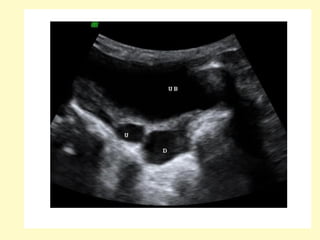

A view from a voiding cystourethrogram demonstrates two large

bladder diverticula (D) flanking the bladder lumen (B), these

diverticula are in the region of the insertion of the ureters, they are

frequently associated with reflux (Hutch diverticula) but no reflux

was demonstrated in this patient